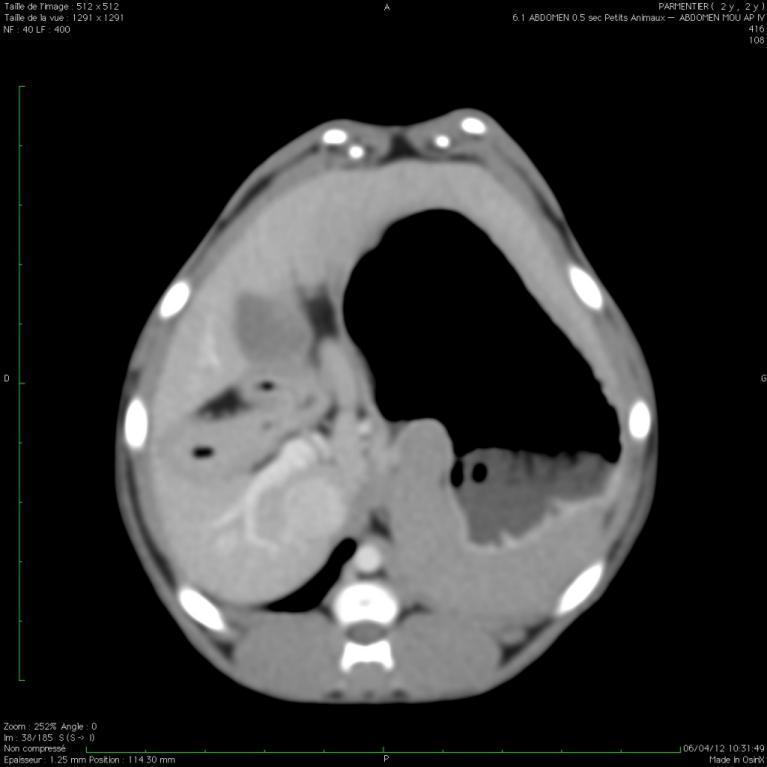

Les scanners abdominaux:

Le scanner n'est pas l'examen le plus utilisé en médecine vétérinaire pour explorer un abdomen: son prix est prohibitif alors que l'échographie, moins honereuse, apporte déjà beaucoup d'information ...

Scanner normal d'abdomen

Scanner normal d'abdomen: produit de contraste au niveau de la veine porte pour une recherche de shunt

SCANNER ABDOMINAL INTEGRAL